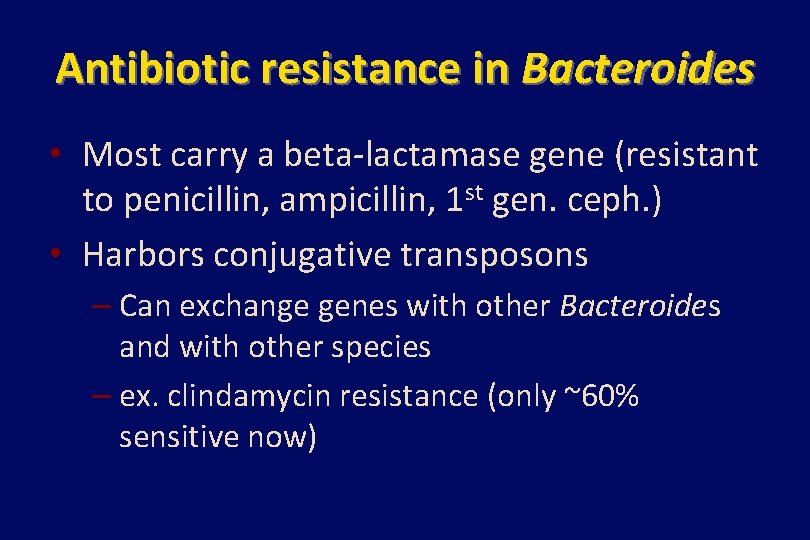

Antibiotic resistance in Bacteroides • Most carry a beta-lactamase gene (resistant to penicillin, ampicillin, 1 st gen. ceph. ) • Harbors conjugative transposons – Can exchange genes with other Bacteroides and with other species – ex. clindamycin resistance (only ~60% sensitive now)